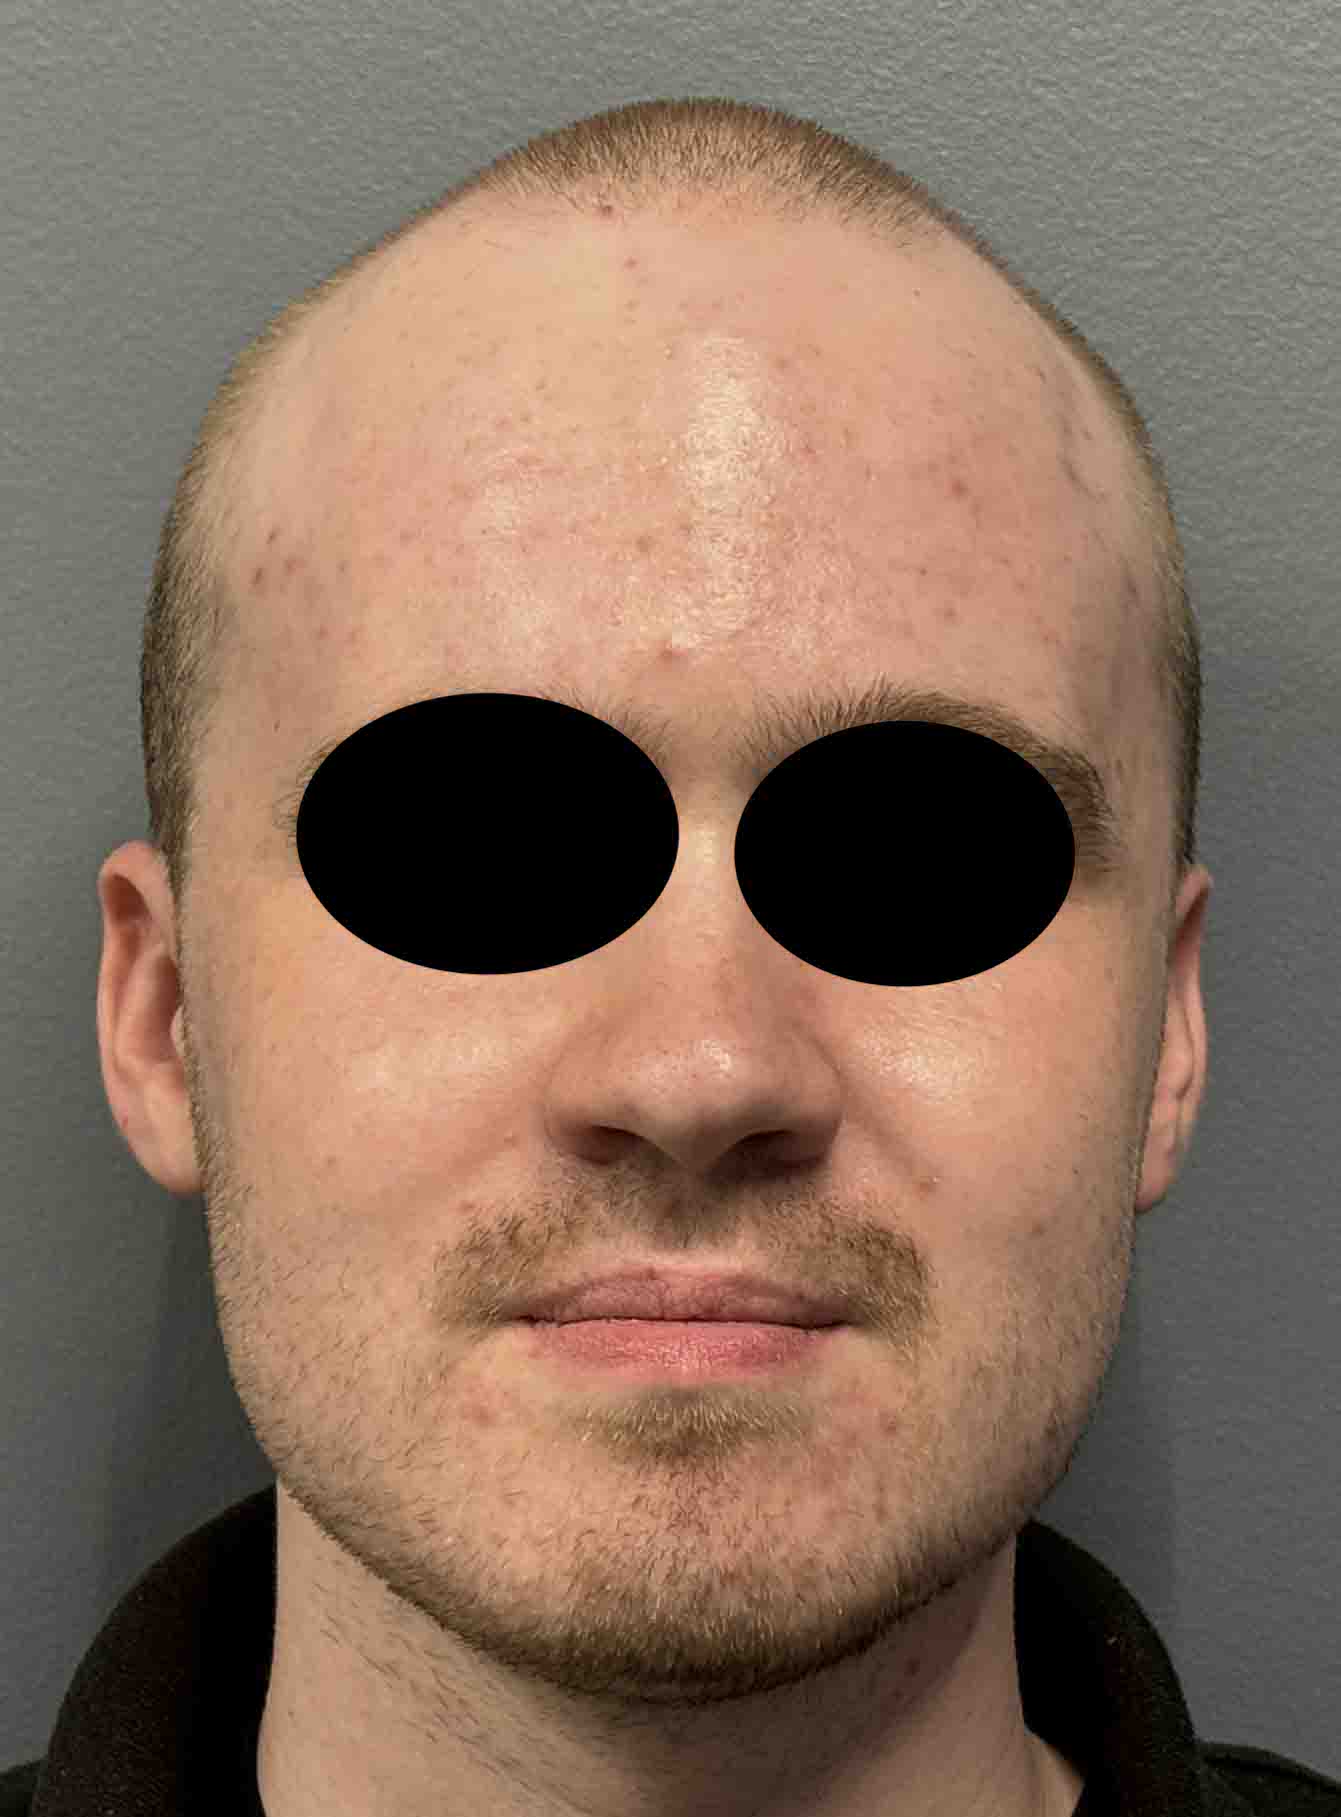

Patient 100

Desire for reshaping of an asymmetric flat back of the head in a shaved head male.

A combined back of the head reshaping procedure was done with a custom skull implant, sagittal ridge reduction and a right temporal muscle reduction.

Desire for reshaping of an asymmetric flat back of the head in a shaved head male.

A combined back of the head reshaping procedure was done with a custom skull implant, sagittal ridge reduction and a right temporal muscle reduction.